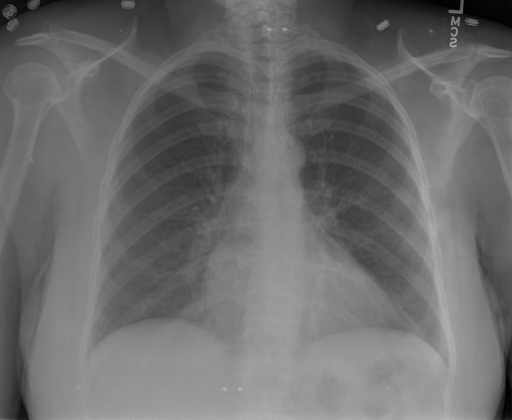

|X光影像|诊疗报告(医生)|XrayGLM|

|:-|:-|:-|

||根据X射线图像,心脏大小正常,肺部看起来很清晰。已经排除了肺炎、积液、水肿、气胸、腺病、结节或肿块的存在。该发现表明一切正常。换句话说,总体印象是胸部正常。|X光片显示,心脏大小正常。肺部没有气胸或胸腔积液的证据。骨骼结构看起来没有任何异常。总的来说,X光片表明没有发现急性心肺疾病的迹象。|